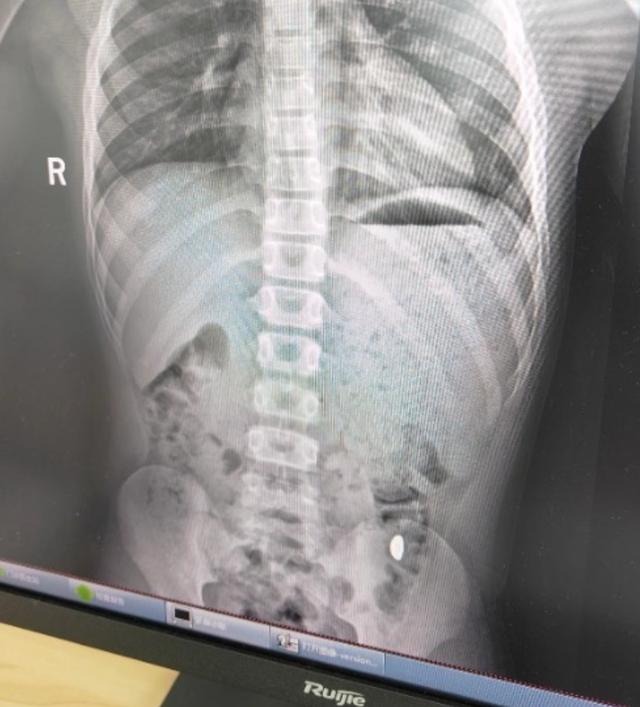

昆山市第五人民医院门诊病历单显示 ,患儿5天前误吞约10克黄金,其间解两次大便未发现,目前无腹痛 、呕吐等症状 ,诊断结果显示胃内有异物。

右下加亮点为金豆 。